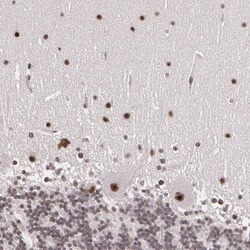

Supportive validation

- Submitted by

- Invitrogen Antibodies (provider)

- Main image

- Experimental details

- Immunohistochemical analysis of C6orf15 in human cerebellum using C6orf15 Polyclonal Antibody (Product # PA5-51577) shows strong nuclear positivity in purkinje cells and cells of molecular layer.